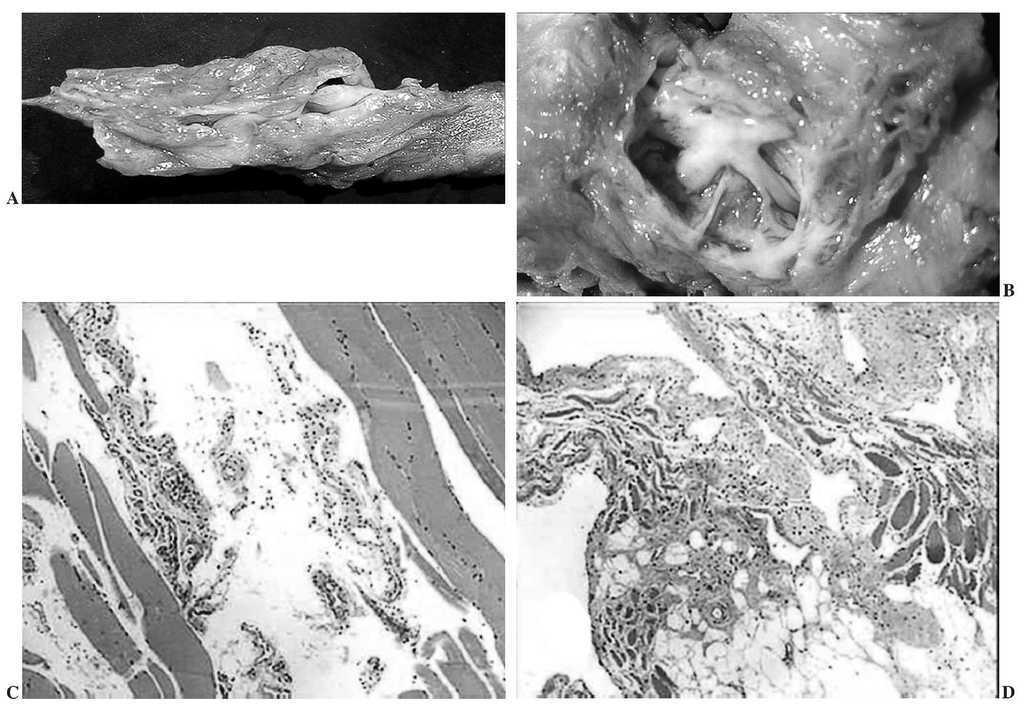

La radiografía simple es anodina. La resonancia magnética nuclear (RMN) inicial informa de "masa redondeada intramuscular en tercio inferior de vasto externo cuadricipital derecho de 4 cm de diámetro mayor, con gran posibilidad de tumor quístico", aconsejándose biopsia lesional. Tras la resección marginal se diagnosticó anatomopatológicamente como "malformación vascular intramuscular benigna". A los 17 meses de la resección marginal presenta recidiva lesional. La nueva RMN (figs. 1A, 1B y 1C) muestra lesión isointensa respecto al músculo circundante en T1 e hiperintensa en T2, con 9 x 4 x 3 cm de diámetros mayores, decidiéndose extirpación lesional radical, detectando macroscópicamente una masa pardo-oscura entre tejido muscular estriado de 14 x 6 cm de diámetros mayores, presentando al corte una zona excéntrica, angiomatosa, mal definida, con un tamaño de 2,5 x 1,5 cm, compatible con hemangioma ectásico congestivo de aspecto cavernoso (figs. 2A y 2B); microscópicamente posee vasos de calibre y espesor parietal variables entre tejidos muscular y fibroadiposo (figs. 2C y 2D). Esta última biopsia permitió el diagnóstico final de hemangioma cavernoso intramuscular del vasto externo cuadricipital derecho. La evolución fue satisfactoria, y hasta la fecha, con un seguimiento ambulatorio de 4 años, no presenta signos de recidiva.

Figura 1.Imágenes de resonancia magnética nuclear del tercio inferior del muslo derecho. (A) Corte axial en T2, apreciándose masa tumoral hiperintensa en músculo vasto externo. (B) y (C) Cortes coronales ponderados en T1, con imagen tumoral prácticamente isointensa respecto a la musculatura circundante, con refuerzo hiperintenso en periferia tumoral.

Figura 2.(A) Masa tumoral resecada; pieza macroscópica. (B) Detalle de pieza macroscópica: imagen estrellada de la zona tumoral. (C) Imagen microscópica (hematoxilina-eosina x 20): plano interfascicular con tejido fibrótico, canales arteriovenosos englobados entre fibras de tejido muscular estriado. (D) Imagen microscópica (hematoxilina-eosina x 20): vasos tortuosos de variable calibre; endotelio sin rasgos de atipia.